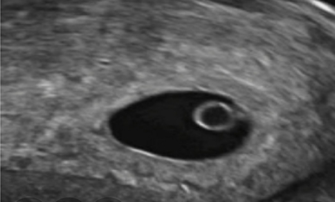

In deze periode maakt het embryo nog gebruik van een zogenaamde voedingsvoorraad uit de dooierzak. Het dooierzakje is zo’n twee weken na de bevruchting al ontstaan en groeit vervolgens door. Naast het voorzien in voedingsvoorraad voor het embryo maakt de dooierzak zwangerschapshormoon aan, waardoor er niet opnieuw een eisprong zal plaatsvinden en waardoor het opgebouwde baarmoederslijmvlies intact blijft. Als je 5 weken zwanger bent kan je het dooierzakje zien op de echo. Het is op dat moment groter dan het embryo zelf. Op de echo zie je het dooierzakje terug als een ringetje, dat samen met het embryo in de vruchtzak ligt. Je kan het dooierzakje zien als een soort knapzakje met extra’s voor de eerste embryonale fase. Zodra de placenta helemaal is aangelegd en volledig functioneert vervalt de functie van de dooierzak, maar dit zal nog een aantal weken duren.